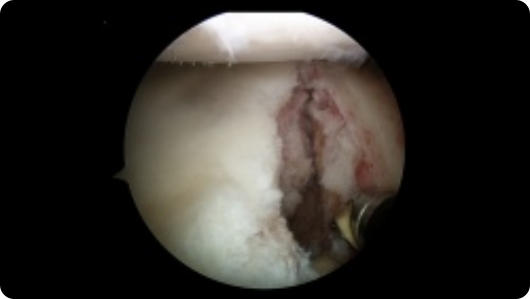

Arthroscopic image of an ACL tear Arthroscopic image of an ACL reconstruction

ACL Tear

ACL Reconstruction